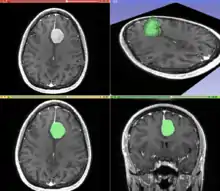

Segmentation

Segmentation is the process of partitioning an image into different meaningful segments. In medical imaging, these segments often correspond to different tissue classes, organs, pathologies, or other biologically relevant structures.[1] Medical image segmentation is made difficult by low contrast, noise, and other imaging ambiguities. Although there are many computer vision techniques for image segmentation, some have been adapted specifically for medical image computing. Below is a sampling of techniques within this field; the implementation relies on the expertise that clinicians can provide.

- Interactive Segmentation: Interactive methods are useful when clinicians can provide some information, such as a seed region or rough outline of the region to segment. An algorithm can then iteratively refine such a segmentation, with or without guidance from the clinician. Manual segmentation, using tools such as a paint brush to explicitly define the tissue class of each pixel, remains the gold standard for many imaging applications. Recently, principles from feedback control theory have been incorporated into segmentation, which give the user much greater flexibility and allow for the automatic correction of errors.[8]